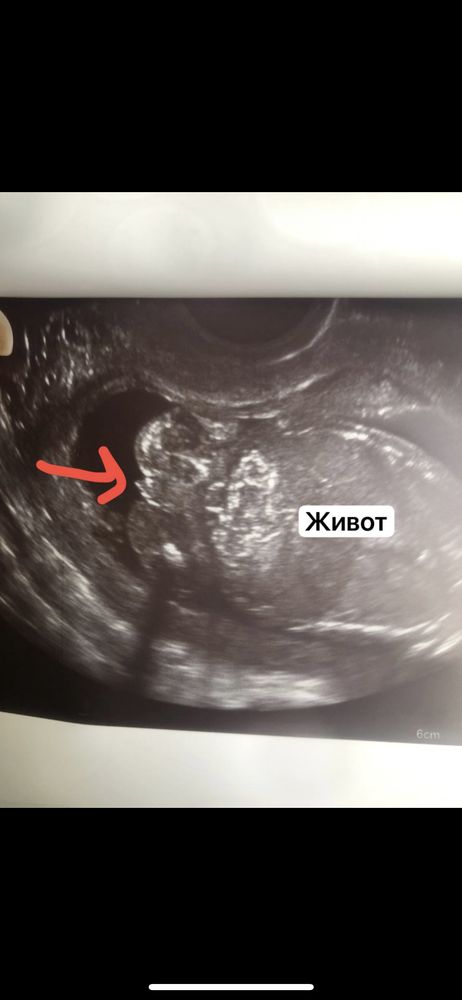

Узи в 16.5 мальчик или девочка ?

Интересно🤔 на фото правда похож на мальчика. Но раз кровь говорит, что девочка… а врач узд вам не сказал пол?

Lady_x, предположила мальчика , поэтому я немного в шоке , по крови ждали девочку

Алена, ну вообще странная ситуация. На таком сроке на УЗИ пол уже хорошо видно, если малыш лежит удобно. Но и анализ крови точнее УЗИ, хотя и тут ошибки случаются, особенно если по результатам девочка (теоретически могут перепутать ДНК матери и плода, такое нечасто, но случается). Если очень любопытно кто у вас, переделаете анализ крови в другой лаборатории, плюс второй скрининг скоро, там тоже пол посмотрят обязательно)

Алена, Если по крови девочка, то девочка))) На узи всяко может привидеться, тем более мы не врачи и тем более срок меньше 20 неделек)) Просто я со своим узи сравнивала. Делала в 15+4. Там примерно в такой позе ничего вообще не торчало))) была выемка даже))) Поэтому и подумала что на фото мальчик))

Алена, как мне врач УЗИ говорила на таком сроке может и клитор у девочки быть большим, пока не закрыт большими половыми губами, у меня мальчики выглядели по другому, но тут и ракурс имеет значение большое. Мне кажется девочка

Пол Пол ребенка 13 недель